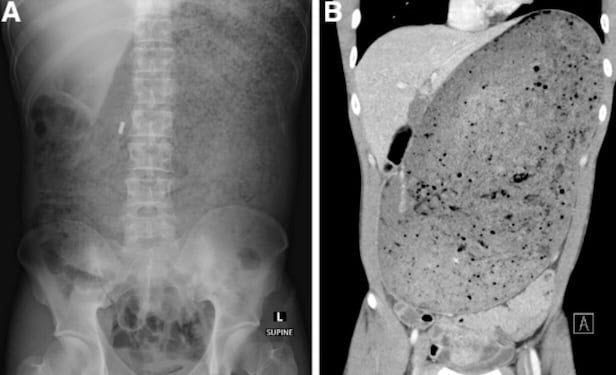

병원에서 CT 촬영 결과 A씨의 위와 십이지장은 섭취한 음식물로 인해 거대하게 늘어난 모습이었다. 소화되지 않은 음식물은 주변의 장기를 압박하고 있었고 췌장은 으스러져 있었다.

실제 공개된 CT 사진을 보면 배꼽 위부터 어깨 부근까지 음식물로 가득 차 있는 모습이다.